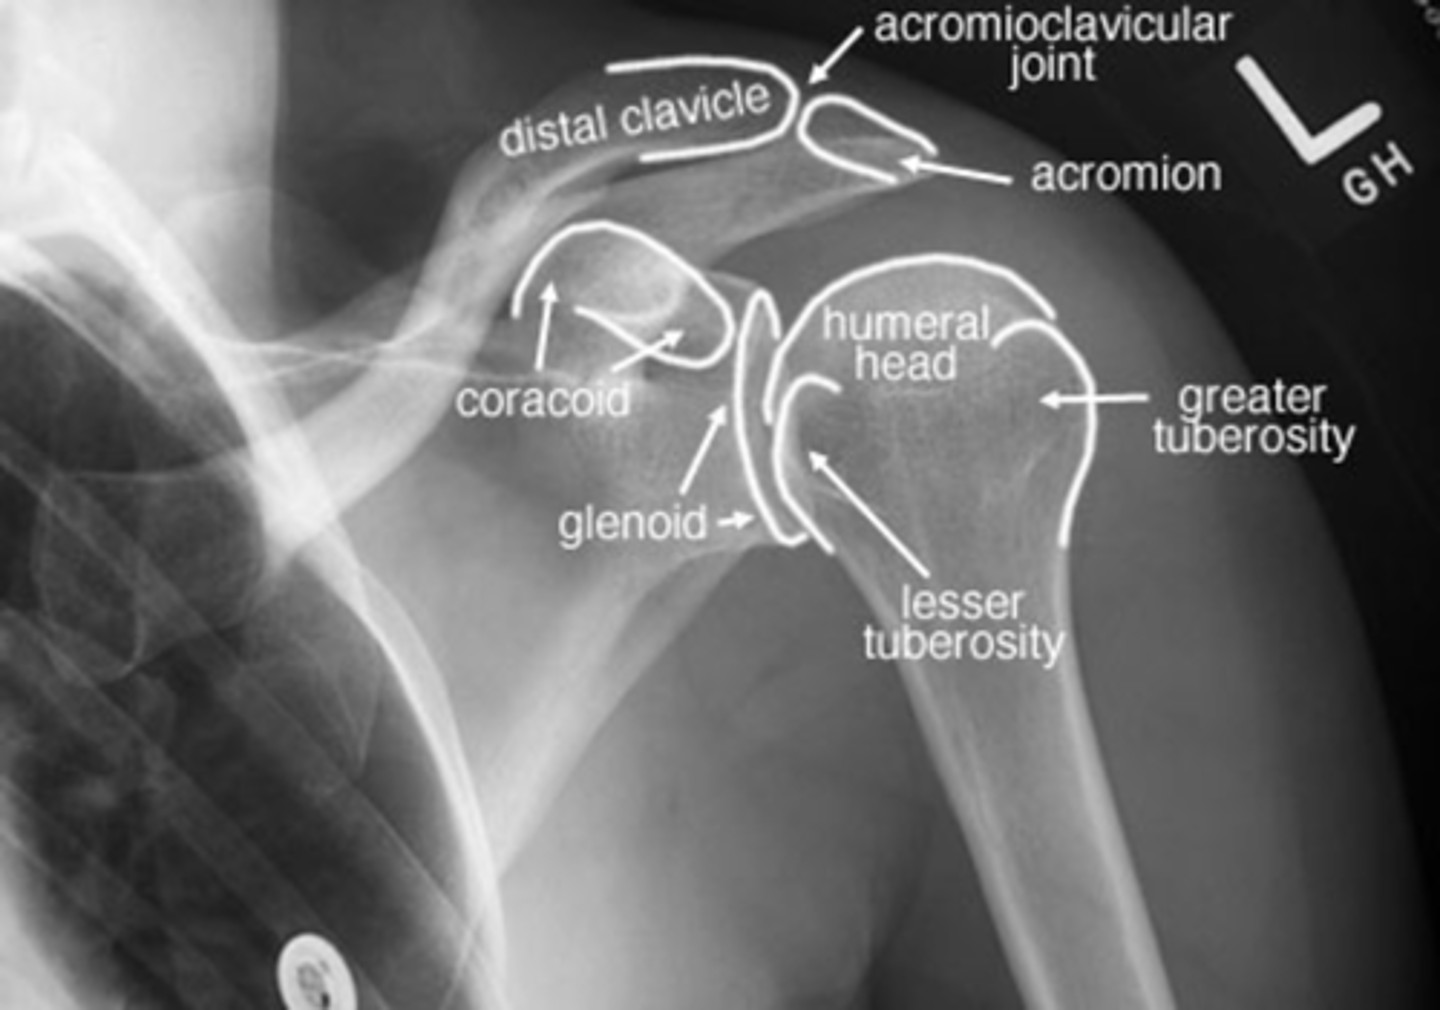

Label this image.

1. Distal clavicle

2. Coracoid

3. Glenoid

4. Head of humerus

5. Lesser tuberosity

6. Greater tuberosity

7. Clavicle

8. AC joint

INTERNAL, because the lesser tuberosity is positioned medially vs. in line with the greater tuberosity, as seen in external rotation

Is this shoulder in EXTERNAL or INTERNAL rotation? Why?